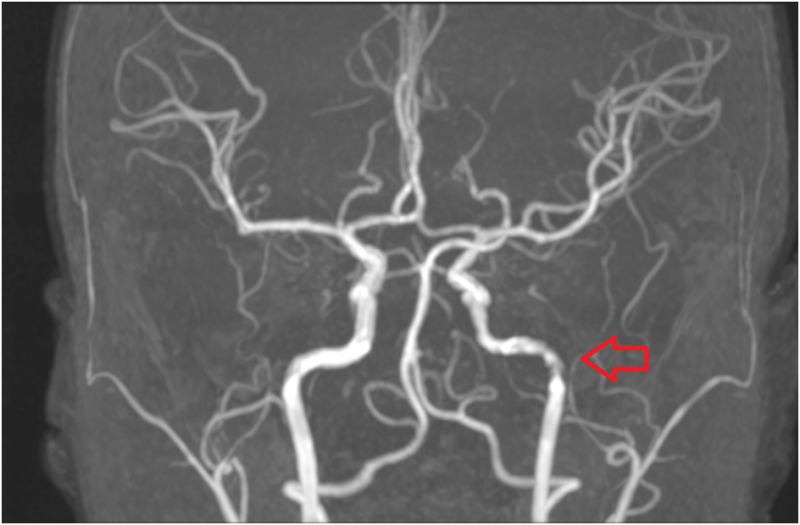

검사결과 #뇌혈관협착(#뇌혈관질환) 빨간 화살표는 왼쪽 뇌혈관이 좁아진 부위를 나타내며 환자의 증상과 일치하여 뇌혈관협착으로 인한 두통으로 확인되었습니다. 환자는 추가 조치(치료, 수술)가 필요한 상황에서 상급병원으로 전원되었습니다.